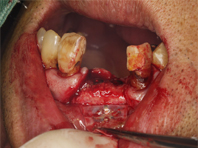

1.

歯茎を切開して拡げてみると骨がなくなっています。

2.

歯を抜いた部分にインプラントを埋入するが、骨がなく、インプラントがほとんど見えている状態です。